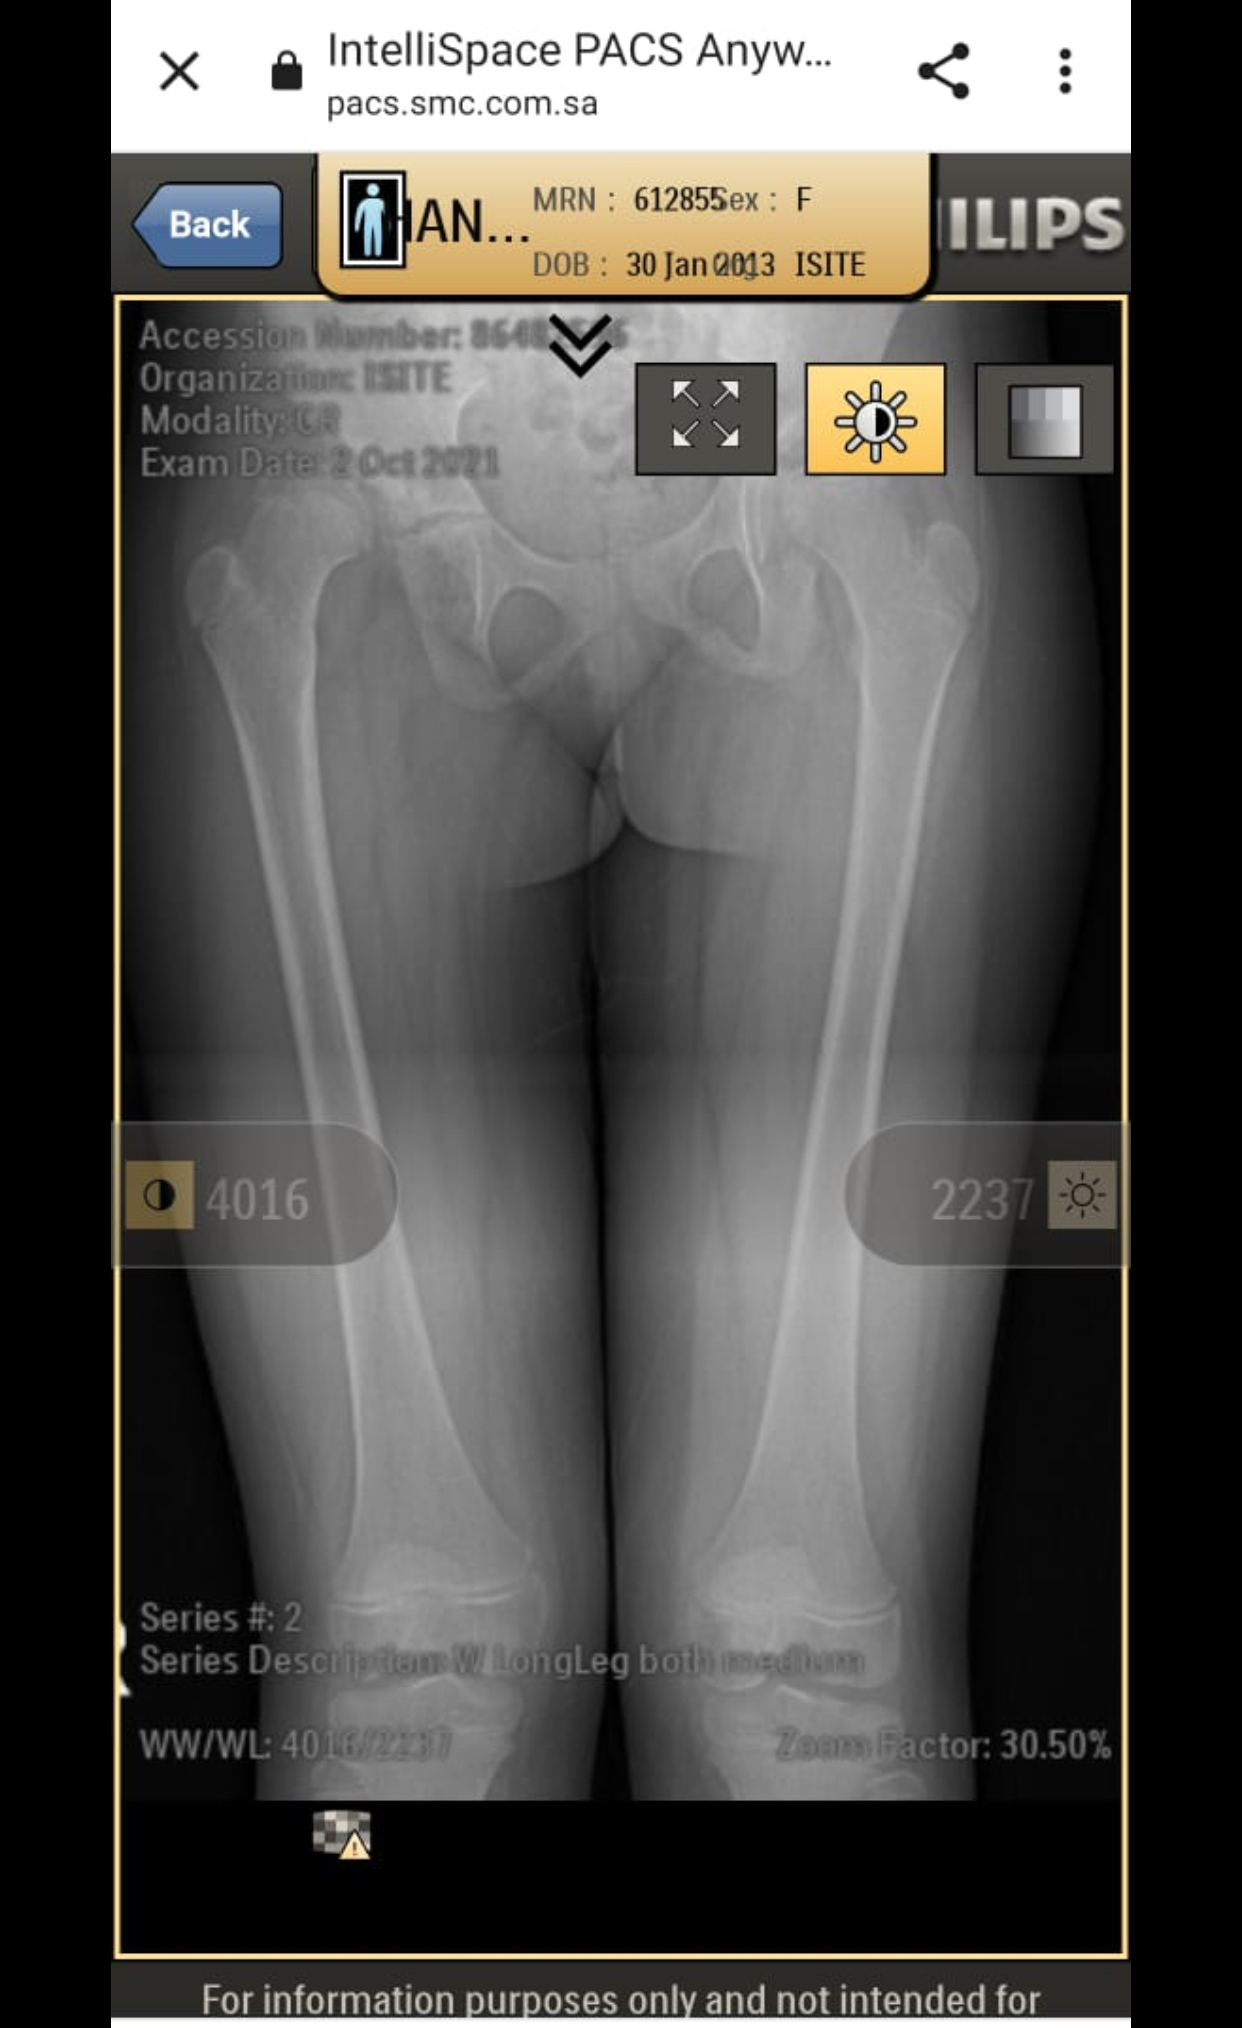

My daughter is diagnosed with hip dysplasia at age of 8.8 years. Doctor is saying for surgery immediately but we got another opinion and that surgeon is saying that there is no success rate of surgery right now. You have to wait once she grow up n then we will go for hip replacement. While the other doctor is saying that surgery is must. We need an opinion on it. Xrays are attached

she definitely need surgery to keep the head at level of socket. you should consult DR. CHIRAGH at GHURKI TRUST HOSPITAL, LAHORE. He is very experienced and expert for this disease.

it needs operation as soon as possible.

Surgery at present at 9yrs of age won't result good results. And re-dislocation may occur soon after surgery. Wait for maturity and then go for translational osteotony/replacement surgery.

Salam, She needs to get MRI of hip joint to measure angles related to hip dysplasia and clinical exam as well before deciding surgery. Thanks